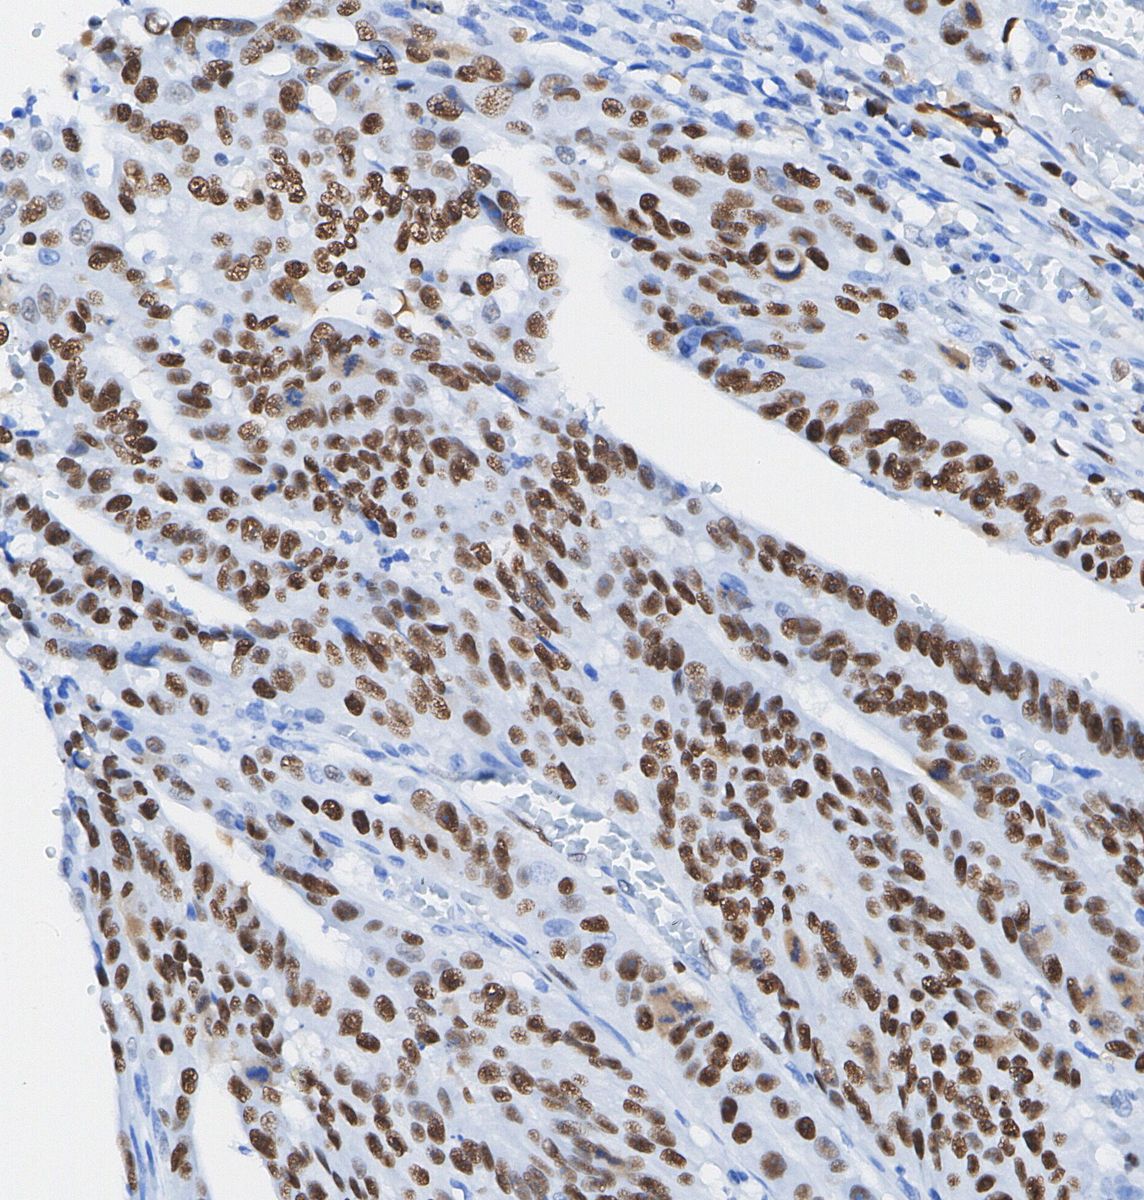

• Immunohistochemical analysis of formalin fixed paraffin embedded human Colorectal cancer tissue with F1002 at 1/100 dilution.

MSH6 Antibody [H6K16] detects endogenous levels of total MSH6 protein.

細胞核、染色体